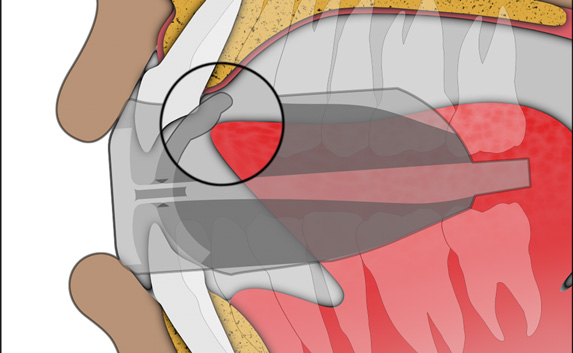

The TMJ Appliance®, which does not require any special fitting, is designed to act as an initial diagnostic and treatment tool for TMJ disorder. It works by decompressing the temporomandibular joint (TMJ), helps to correct mouth breathing and tongue posture habits, as well as limits bruxing. The TMJ Appliance® achieves TMJ disorder symptom relief immediately by alleviating pressure on the TMJ and relaxes the muscles around the jaw and neck.

The TMJ Appliance® treats both intracapsular and extracapsular disorders—TMJ clicking and pain (intracapsular) as well as pain referred from the craniomandibular muscles (extracapsular).